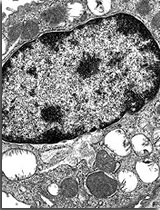

La réparation alvéolaire met en jeu les cellules épithéliales, les fibroblastes alvéolaires, le système de la coagulation et la réparation vasculaire.

La réparation de l’épithélium alvéolaire est cruciale pour la restauration de la barrière alvéolaire. Cependant, une réparation inadaptée conduira au développement d’une fibrose.

Les fibroblastes ont un rôle crucial dans la réparation alvéolaire. Leur présence dans la phase initiale de la pathologie serait un indicateur de guérison.